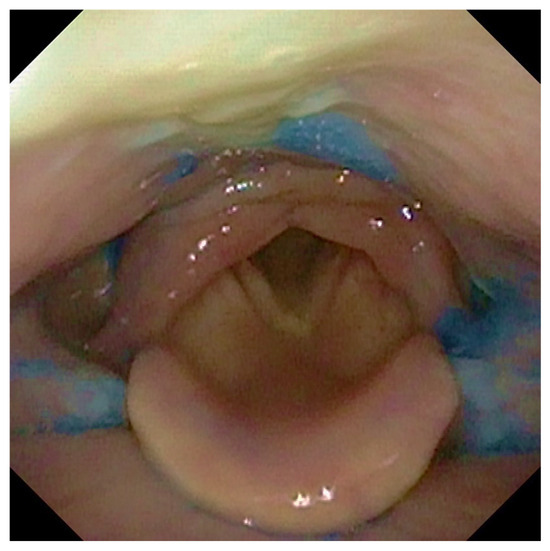

2.3. FEES Protocol